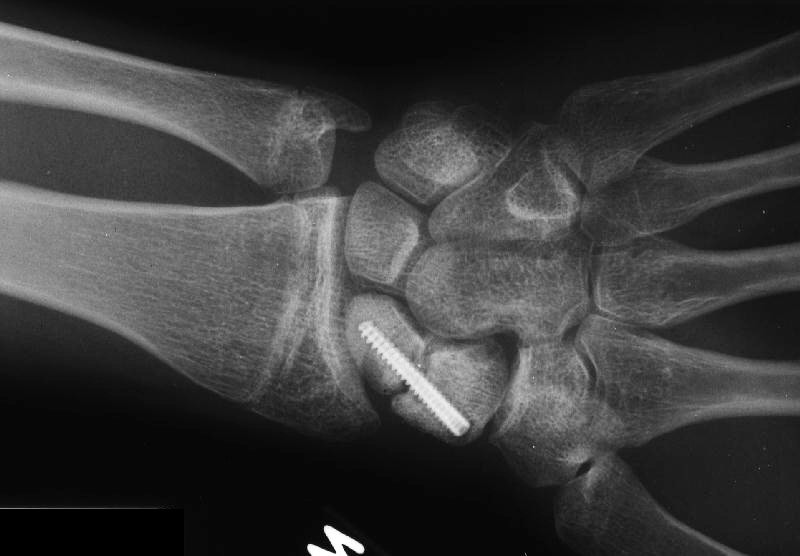

Healed.

The patient requested hardware removal prior to enlisting for military duty. Final films.